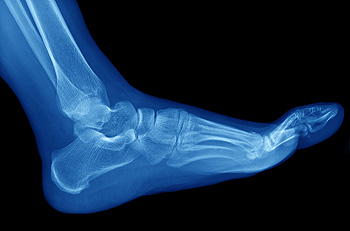

Stress fractures can be common among athletes. They can happen as a result of the consistent pressure that the bones of the feet endure during the athlete’s chosen sport. Stress fractures are defined as small, hairline fractures in the bones which may make walking and running difficult. Common symptoms can include pain surrounding the affected bone, which may improve when the foot is resting and elevated. Some patients experience bruising and swelling, accompanied by achiness. Additionally, stress fractures may gradually develop as a result of wearing shoes that do not fit properly, and this may weaken the foot bones. If you have pain in your foot, it is suggested that you consult with a podiatrist who can diagnose and treat stress fractures.

Stress fractures are the result of repetitive force being placed on the bone. Since the lower leg and feet often carry most of the body’s weight, stress fractures are likely to occur in these areas. If you rush into a new exercise, you are more likely to develop a stress fracture since you are starting too much, too soon. Pain resulting from stress fractures may go unnoticed at first, however it may start to worsen over time.

Stress fractures do not always heal properly, so it is important that you seek help from a podiatrist if you suspect you may have one. Ignoring your stress fracture may cause it to worsen, and you may develop chronic pain as well as additional fractures.